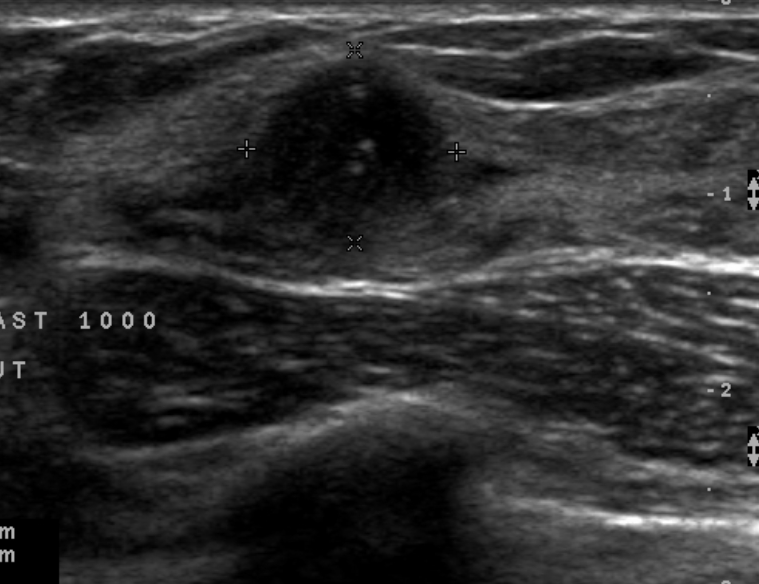

The target dataset was developed from 35 breast ultrasound scans that were segmented by an image-processing expert with extensive experience in breast lesion segmentation (the second author). The images, collected from the Web, are of different dimensions, ranging from to pixels (Figure 3, images resized for sake of illustration). These are the same images used to introduce EFIS originally [1].

Ultrasound images are generally difficult to segment, primarily due to the presence of speckle noise and low level of local contrast. It should be noted that the segmentation of ultrasound actually does require a complete processing chain, (including proper preprocessing and post-processing steps). However, the purpose of using these images was solely to demonstrate that the accuracy of the segmentation can be increased with the application of SC-EFIS.